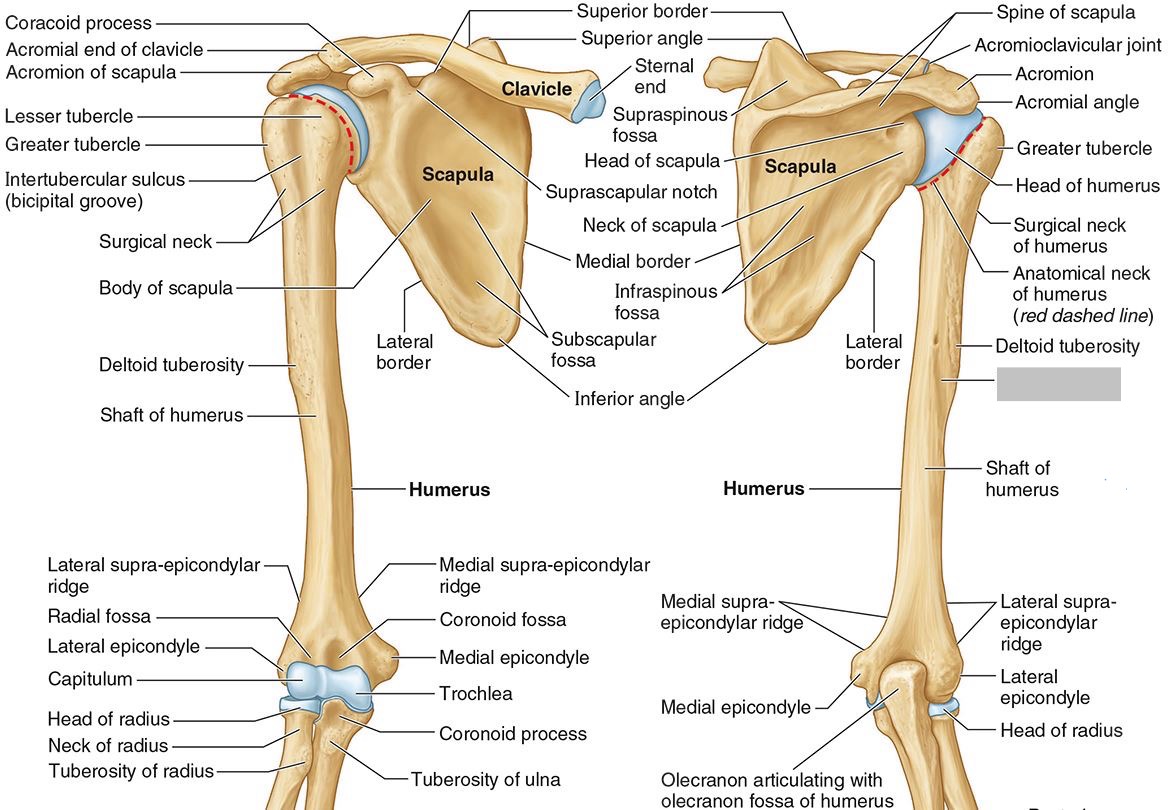

What part of the humerus is this?

The head of the humerus articulates with the scapula at the glenohumeral joint.

What part of the humerus is this?

The anatomic neck is an indentation distal to the head and provides an attachment for the fibrous joint capsule of the glenohumeral joint.

What part of the humerus is this?

The greater tubercle lies lateral and distal to the anatomic neck.

What part of the humerus is this?

The lesser tubercle lies on the anterior/medial side of the humerus, just distal the anatomic neck.

What part of the humerus is this?

The intertubercular (bicipital) groove lies between the greater and lesser tubercles.

What part of the humerus is this?

The surgical neck is a narrow area distal to the tubercles. It is a common site for proximal humerus fractures.

What part of the humerus is this?

The humeral shaft features the deltoid tuberosity laterally for the distal insertion of the deltoid muscle.

What part of the humerus is this?

The radial groove is an oblique depression that contains the radial nerve and deep brachial artery.

Which parts of the humerus is this?

The medial and lateral epicondyles are distal prominences to which many forearm tendons attach, near the elbow joint.

Which parts of the humerus is this?

The medial and lateral supracondylar ridges extend superiorly from the medial and lateral epicondyles.

Which parts of the humerus is this?

The trochlea and the capitulum (the condyles) are the most distal surfaces of the humerus, where it articulates with the forearm bones at the elbow joint

What part of the humerus is this?

The olecranon fossa is a posterior depression above the trochlea that receives that olecranon process of the ulna

What part of the humerus is this?

The coronoid fossa is an anterior depression above the trochlea that receives that coronoid process of the ulna.